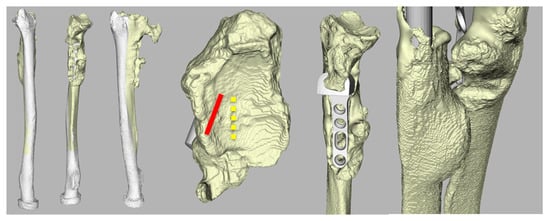

2.5. Radiographic Assessment

3.3. Radiological Evaluation

| Case | Radiological Evaluation | Combined Error | Translation Healthy | Translation Aptis | Δ Translation |

| 1 | Periprosthetic fracture; proximal screws | 11 | 1.5 | 0.5 | −1.0 |

| 2 | Lucency distal screw (37) | 6 | 2.8 | 0.6 | −2.2 |

| 3 | Heterotopic ossification (8) | 7 | 1.3 | 0.2 | −1.1 |

| 4 | No abnormalities | 5 | 2.8 | 0.5 | −2.3 |

| 5 | Heterotopic ossification (4) | 12 | 2.7 | 3.5 | 0.8 |

| 6 | - | 7 | 1.4 | 4.1 | 2.7 |

| 7 | Heterotopic ossification (5) + Lucency distal screw radius (13) | 14 | 2.1 | 0.3 | −1.9 |

| 8 | No abnormalities | 6 | 1.6 | 0.3 | −1.3 |

| 9 | Chip distal ulna (7) + Heterotopic ossification (24) | 13 | 1.8 | 0.3 | −1.5 |

| 10 | Dystrophic calcification (1.5) | 10 | 2.4 | 0.4 | −2.0 |

| 11 | Lucency distal screw (8) + heterotopic ossification (48) | 10 | 1.9 | 2.0 | 0.1 |

| 12 | Heterotopic ossification (57) | 9 | 1.7 | 0.3 | −1.4 |

| Average (SD) | 9 (3) | 2.0 (0.6) | 1.1 (1.3) | −0.9 (1.4) |